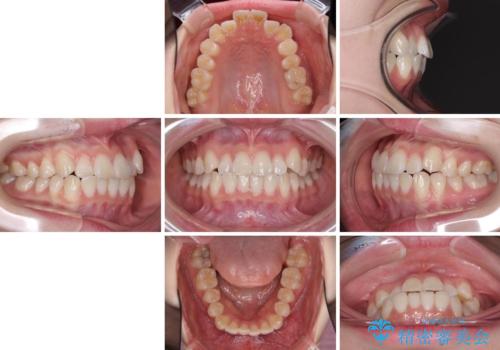

- 海外留学の予定があるが、学生のうちに歯列を整えたいとのことで来院された患者様です。

前歯にデコボコがあり、口元がやや突出した印象があったため、IPR(歯と歯の間を削る)と親知らずを抜歯した上での歯列全体の後方移動をメインに、インビザラインを用いて矯正治療を行うこととしました。

海外留学前にインビザラインをしっかりと使用できるようにし、現地での治療の進め方や帰国時の対応を決めた上で治療を開始しました。

年に一度、夏休みの時期にしか帰国できないため、帰国のタイミングに合わせてマウスピース交換スケジュール治療計画としたため、3年半という期間を要しました。

留学先でもしっかりとマウスピースの装着を実践してくださったので、ご本人の満足のいく仕上がりとなりました。